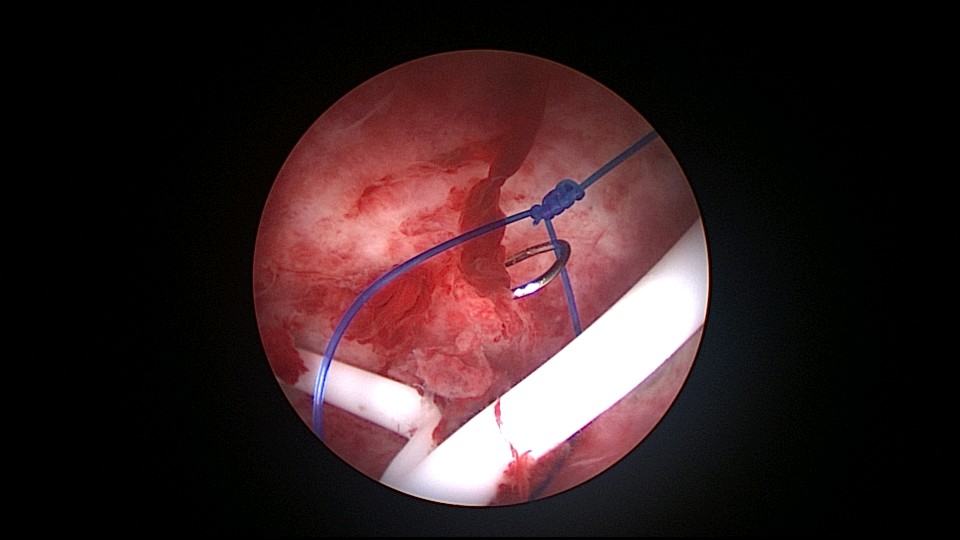

患者39岁,G6P1,顺产1次。2022年5月因输卵管间质部妊娠行宫腹腔镜手术(术前门诊医生诊断宫角妊娠),腹腔镜下行左侧输卵管间质部妊娠套扎开窗取胚术,术中见子宫腺肌症结节明显。2025年3月,严重痛经,皮下注射亮丙瑞林已3个周期,行经第6天,放置曼月乐并固定,拟行缝合固定,宫腔镜下缝合一针,牵拉确认缝合到肌层,推结时缝合处撕裂,拉出曼月乐,立即改为挂钩固定。先将不锈钢挂钩插入宫底肌层,4-0不可吸收线在曼月乐横臂中间套扎形成线圈,将曼月乐置入宫腔,异物钳夹持线圈挂到不锈钢挂钩里,原位固定曼月乐,退出宫腔镜,结束手术。2025年5月复查B超,节育环距宫底3cm,查看图片,线圈较大。节育环距宫底距离跟子宫大小、宫壁厚度、挂钩长度及线圈长度之和有关,保持这个距离不再延长即为手术成功。